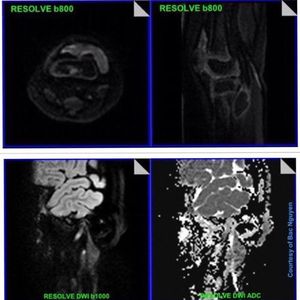

Extracranial DWI is now widely applied in clinical practice to enhance disease assessment and research into its application in the MSK system has been growing. RS-EPI (RESOLVE) is a revolutionary new approach for obtaining high-quality, high-resolution DW images even in body regions strongly affected by susceptibility artifacts, such as MSK (figure). RESOLVE uses the same diffusion preparation as single-shot EPI, however, the k-space trajectory is divided into multiple segments in the readout direction, which allows for a TE and and an encoding-time reduction increasing image quality. Images courtesy of Nguyen Bac.